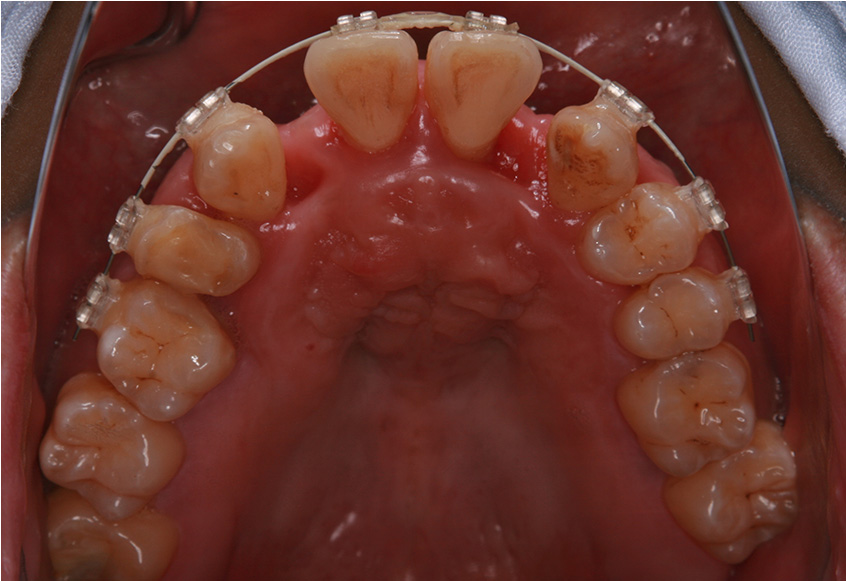

最初のお口の中 ワイヤー装着して治療を開始

-